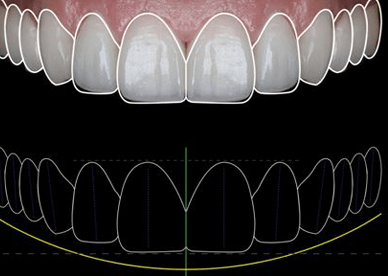

Implantes dentales en Madrid – calidad y precio en Barrio Salamanca En Dr. Alejandro Prieto Dental Clínica Dental, tu clínica dental de confianza en el Barrio Salamanca de Madrid, somos expertos en implantes dentales de todos los tipos. Mezclamos implantología avanzada con alta estética. Si estás buscando una solución duradera, estética y con precios competitivos, […]